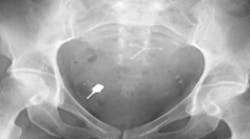

As the idiom goes, an ounce of prevention is worth a pound of cure. In this case, five seconds of diligence can prevent five years of agonizing litigation should an unexpected outcome develop during implant rehabilitation (figure 5).

Figure 5